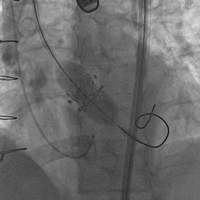

病例五(经股动脉主动脉瓣瓣中瓣)

患者男性,71岁,胸痛、气短半年,近一月加重,既往行主动脉瓣生物瓣置换术,置入HANCOCK II 21#瓣膜。术前心脏超声示主动脉瓣生物瓣衰败,主动脉瓣重度狭窄并中度关闭不全,峰值流速3.8m/s,平均跨瓣压差23mmHg。STS评分8.046%,属于外科换瓣手术高风险患者。术中经股动脉途径植入19#Renato球扩式瓣中瓣,释放成功后瓣膜功能良好,无瓣周漏及瓣中反流。峰值流速降至2.5m/s,平均跨瓣压差降至12mmHg。

瓣膜释放 术后主动脉根部造影无反流